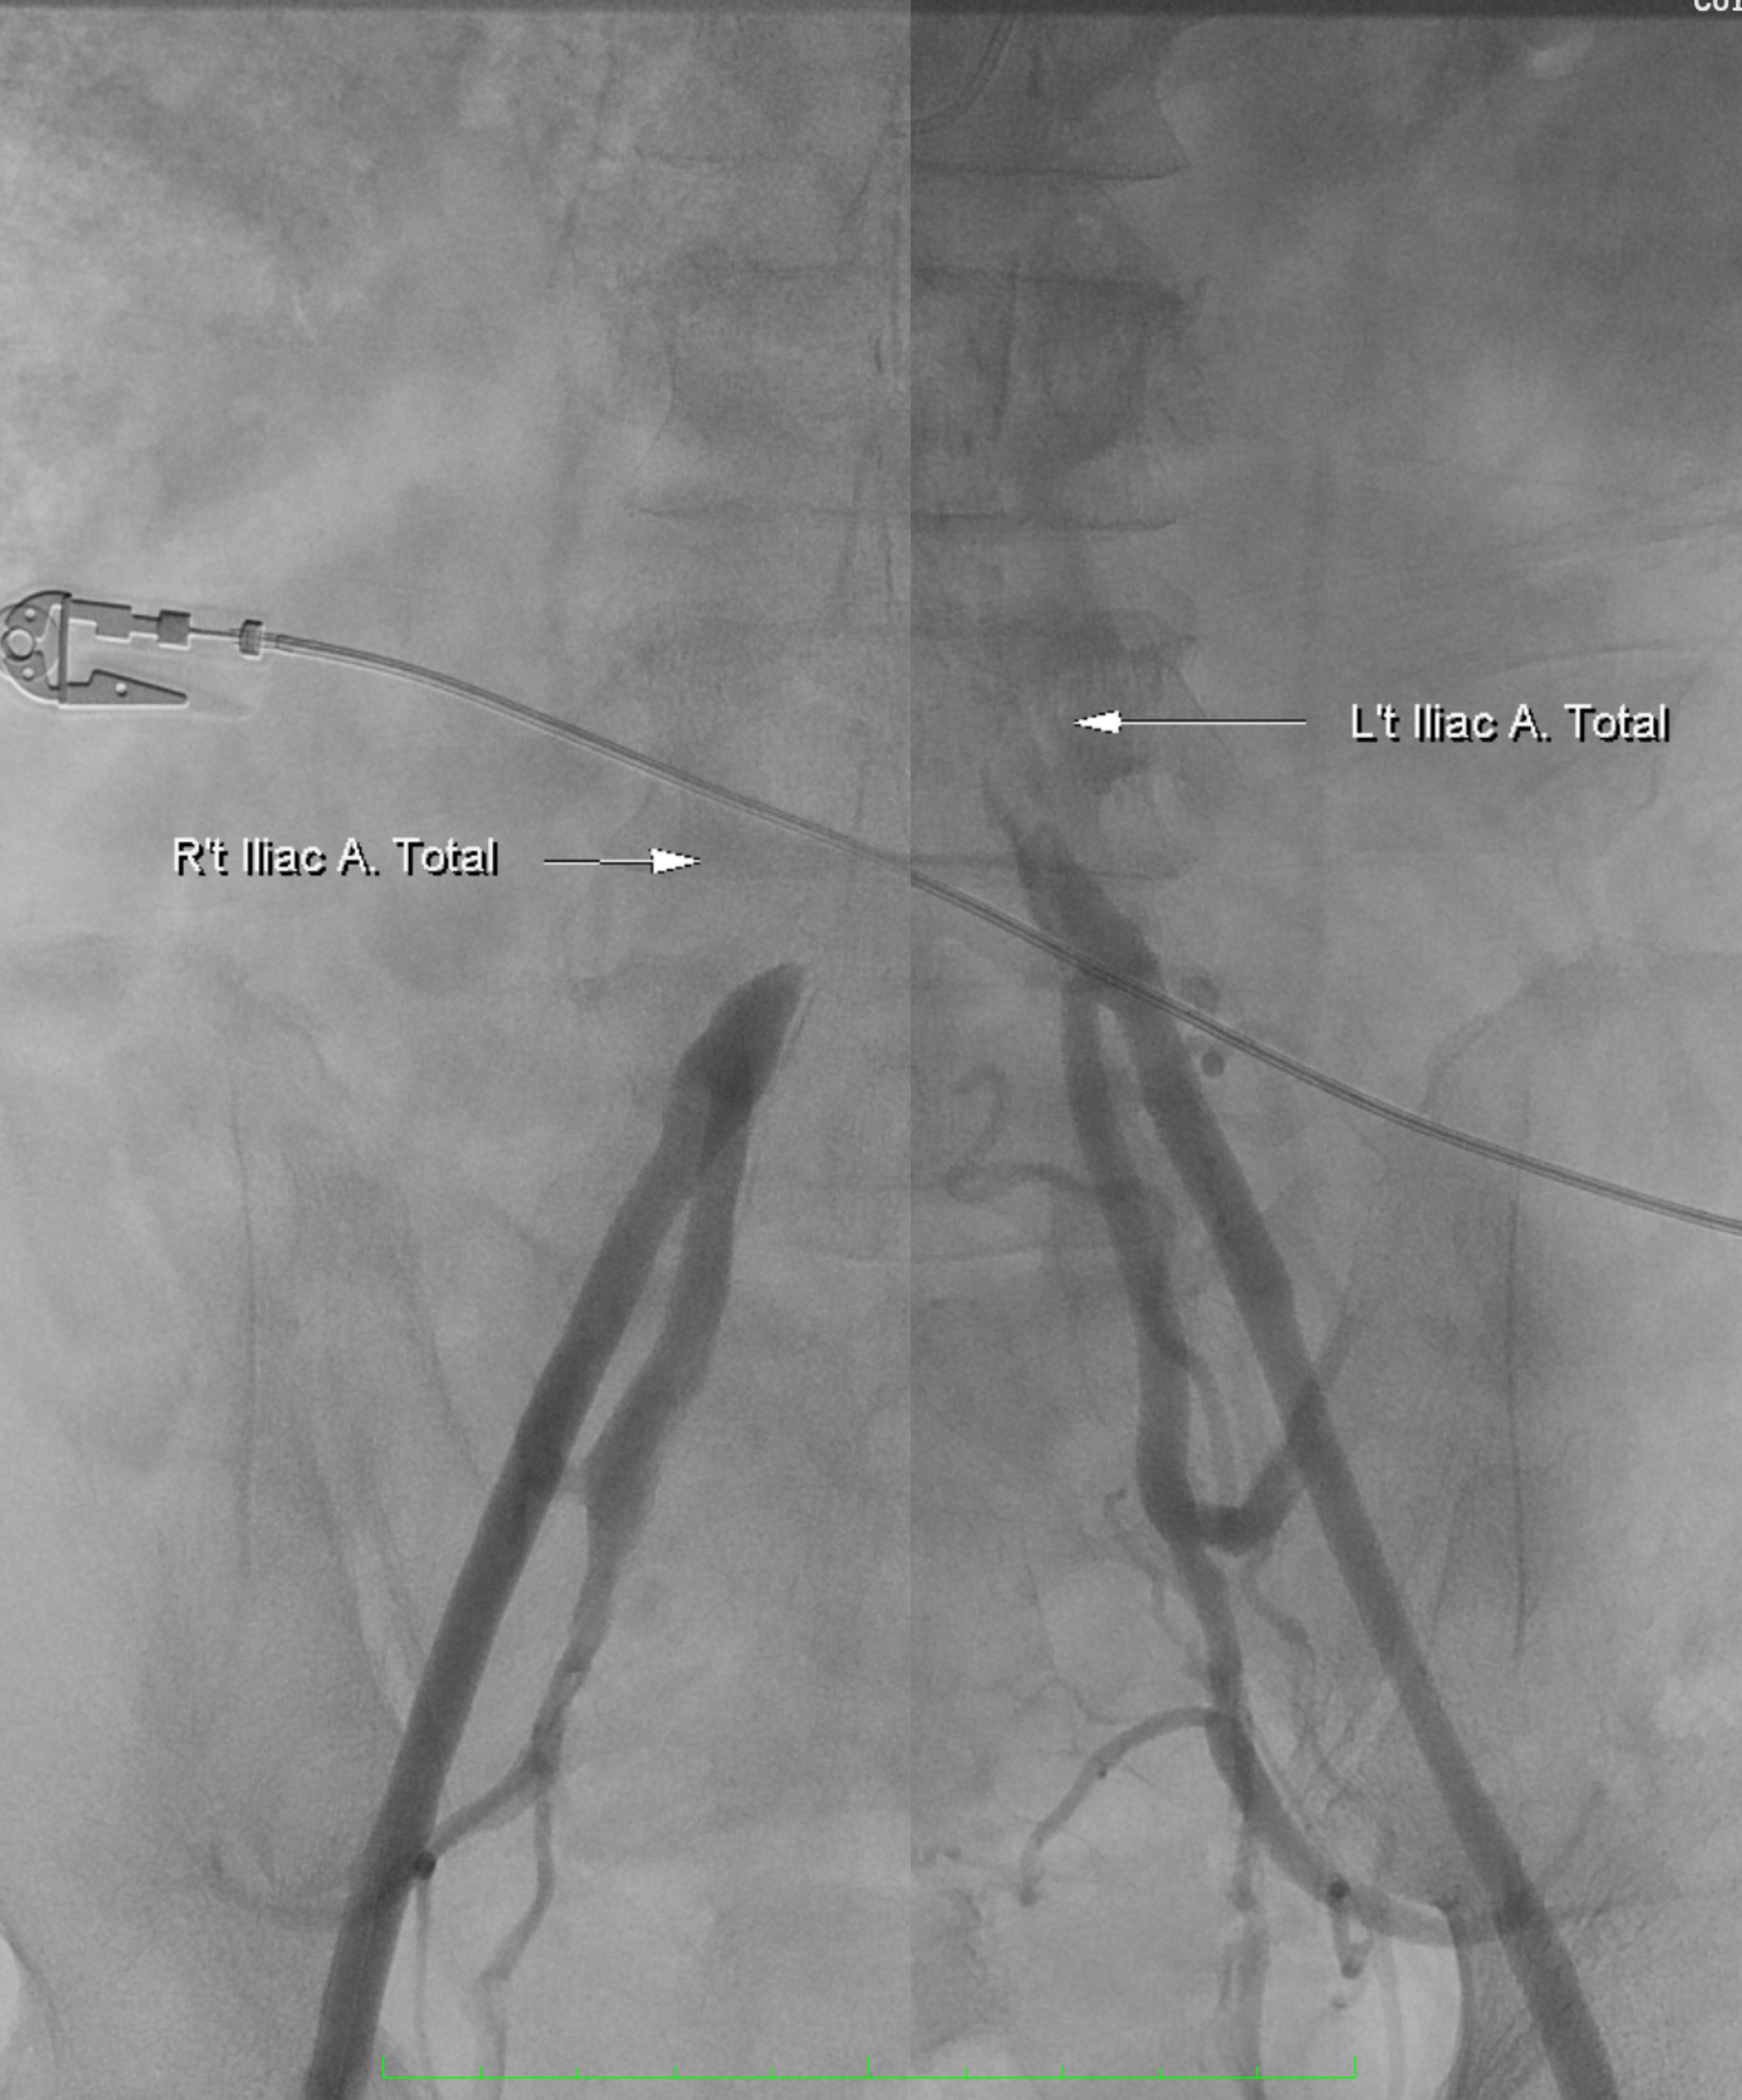

Relevant Catheterization Findings

Diagnosticangiography revealed total occlusion of both common iliac arteries, while theexternal iliac arteries remained patent bilaterally. The lesions wereconsistent with aortoiliac occlusive disease (Leriche syndrome), and the distalflow was preserved via collateral circulation.

A 6F Mach1 MP guiding catheter waspositioned via aterial access. Wiring was performed sequentially with Gladius0.014¡È and Halberd 0.014¡È under NaviCross 0.018¡È catheter support, then switched to an Astato XS 40 for bettercontrol. Using a CSI microcatheter, the 0.018¡È system was exchanged for a 0.014¡È wire to performIVUS. IVUS initially could not advance but succeeded after predilatation withan Ultraverse 2.0 balloon. IVUS revealed that the lesion was locatedclose to the inferior mesenteric artery and provided accurate vessel sizing forappropriate stent selection. The system was then switched back to the 0.018¡È platform forintervention. Balloon dilatations were performed using Ultraverse 5.0 ¡¿ 80 mmfor the right and 7.0 ¡¿ 40 mm for the left common iliac artery, followed bysimultaneous kissing balloon inflation. Further expansion was achieved with Armada8.0 ¡¿ 80 mm balloons. Two VBX 8.0 ¡¿ 59 mm heparin-bonded stent grafts weredeployed in the right and left common iliac arteries. A subintimal flap belowthe right CIA stent edge required an additional VBX 8.0 ¡¿ 39 mm stent.Post-dilatation was performed with a Finestream S Plus 8.0 ¡¿ 40 mm andUltraverse 7.0 ¡¿ 80 mm balloon using the final kissing technique. Final angiography demonstrated well-expandedstents and excellent bilateral flow without residual stenosis or dissection.Both femoral access sites were closed with ProGlide devices, and the leftradial sheath was removed with manual compression.